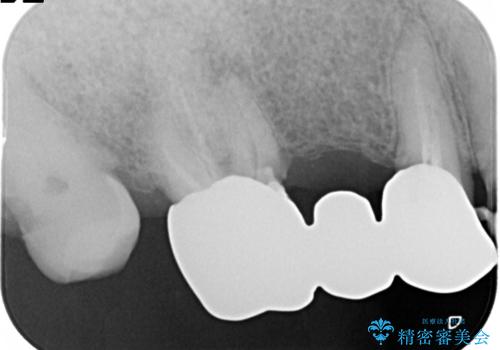

- 奥歯がなくて咬めないのと、全体的に見た目をよくしたいとのことで来院されました。

下顎の両側の奥歯が欠損しており、入れ歯をお持ちでしたが、うまく咬めずにほとんど使用していない状態でした。

上顎は全体的にクラウンの入れ替えと、下顎はインプラントの提案もしましたが、希望されなかったのでノンクラスプデンチャーの製作をする治療計画としました。

奥歯が欠損しており、上下の前歯が強く咬合する可能性があったので、上顎前歯の裏側は金属のものにしました。

お忙しい方でしたので、治療が終了するまでにじかんがかかってしまいましたが、奥歯でもしっかり咬めるようになったと喜んでいただけました。